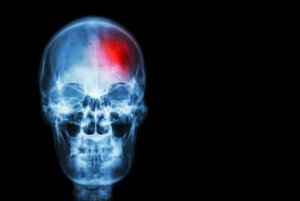

I de enkleste termer er et slag et tap av blodsirkulasjon til hjernen. Risikoen øker etter hvor lenge hjernen er fratatt oksygen på grunn av mangel på blodstrøm.